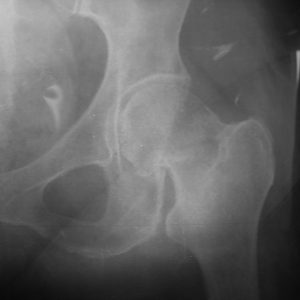

Η διάγνωση του κατάγματος ισχίου ξεκινά με λεπτομερή κλινική εξέταση και επιβεβαιώνεται με ακτινογραφία της περιοχής του ισχίου σε δύο προβολές.

Ο έντονος πόνος στη βουβωνική περιοχή και η αδυναμία φόρτισης του σκέλους θέτουν άμεσα την υποψία κατάγματος ισχίου. Αν η αρχική ακτινογραφία δεν δείξει καθαρά το κάταγμα, αλλά η υποψία παραμένει ιδιαίτερα σε ηλικιωμένο άτομο απαιτείται περαιτέρω έλεγχος.

Επίσης, η μαγνητική τομογραφία διαθέτει υψηλή διαγνωστική ακρίβεια και μπορεί να αναδείξει κατάγματα που δεν είναι εμφανή στην απλή ακτινογραφία.